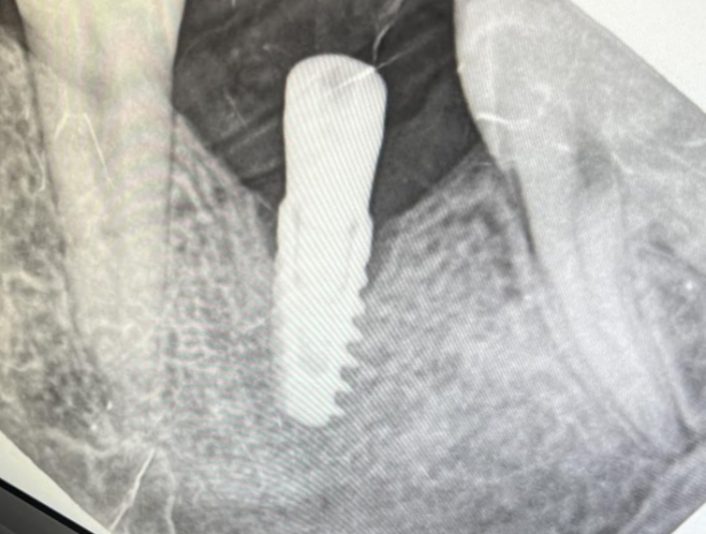

Some of the most rookie mistakes can be a fractured screw of an abudment. It’s really annoying but that involves in some cases. Let’s say you made a perfect All on X case with perfect prothesis all good 👍🏻 till now.…

• Thank you for sharing Mohamed! For those of us who might not understand the first picture. Can you tell us what that is? Is it an abutment that is cold welded to the implant?